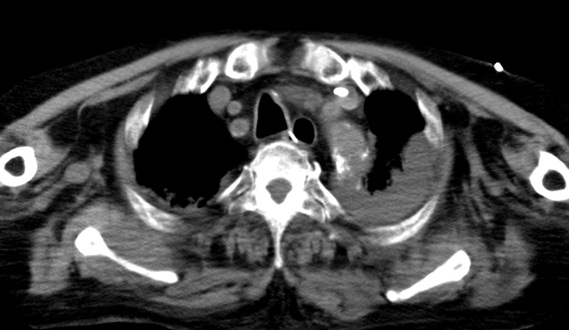

- 9月12日:血胸・緊張性血胸の痕跡

X線・CTで縦隔拡大や胸水の所見あり。輸血が必要になるほどの貧血は心タンポナーデのみでは説明不能。

証拠:胸腹部CT・血胸

この時、同時に撮影された胸腹部CTでは、大動脈周囲に三日月状の血種様の病変が認められ、両胸腔にはフィブリン化したと思われる血餅の残存病変が多数認められた。大動脈損傷に伴い大動脈から胸腔に出血していた証拠であり、当初のPCI(カテーテル治療)での医療事故の痕跡がこのCT画像に残っている。